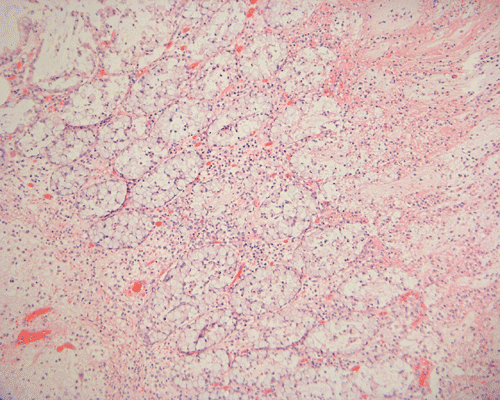

Histopathology: On scanning magnification, the mucosa has a sandwich like structure (Panel A). At the bottom is a layer of partially destroyed glands with a middle layer of mucoid material and topped by a layer of inflammatory exudate (Ž in Panel A). In some areas, the inflammatory exudate takes the shape of a mushroom or volcano (Panel B). The submucosa is edematous but lacks significant inflammatory cell infiltration. The top layer of inflammatory exudate is composed exclusively of degenerated polymorphonuclear leukocytes (Panel C and D). At the base of the mucosa, the outline of the normal glandular architecture is maintained but there is intense infiltration by polymorphonuclear leukocytes in the lamina propria (Panel E and F). On high-magnification, the crypts are filled by signet ring cells. In severely inflammed areas, there are some single singnet ring cells in the lamina propria (Panel G). In the deeper part of the mucosa where inflammation is not as intense, the boundary between the crypts and the lamina is respected by the signet cells (Panel H). In the more superficial part of the mucosa, the glandular architecture is disrupted (Panel I). Sporadic signet ring cells are also found in mucosa that are relatively unaffected (Panel J).

Macroscopically, membranous colitis is featured by erythematous, denuded mucosa with scattered patches of grayish-white to yellow plaques or pseudo-membranes and a thickened lamina propria. Microscopically, the mucosa shows a dense infiltrate of neutrophils within the superficial lamina propria, denudement of surface epithelium, and occasional capillary fibrin thrombi. Mucopurulent exudate fills distended crypts and erupts into the bowel lumen to form a pseudo-membrane adherent to the damaged epithelial surface 5. In the most typical case, the pseudomembrane and the damaged mucosa give resemblance to an erupting vocano.